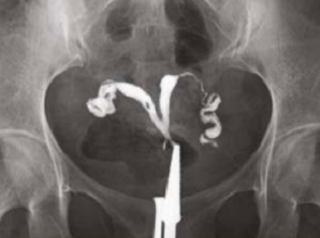

What does HSG assess?

-

Shape of the uterus

Normal shape

Unicornuate uterus

Complete septate uterus

Patency of fallopian tubes

Open tube

Closed tube

Uterine cavity

Clear/Normal

Submucosal fibroid

Adhesions/Synechiae